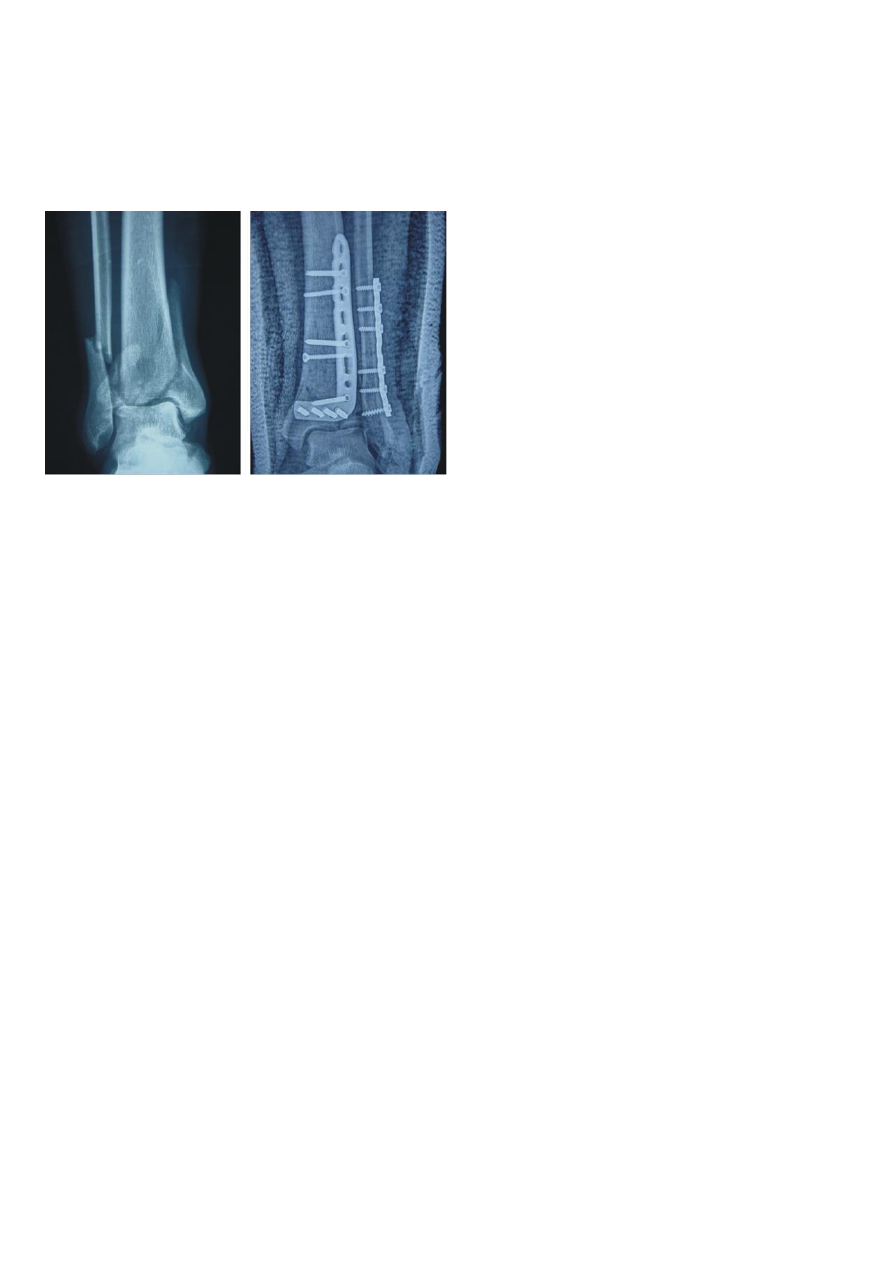

手术治疗

:粉碎性骨折、移位骨折或合并血管损伤者需手术干预,通过钢板、髓内钉等内固定器材恢

复骨骼解剖位置。对于小腿动脉损伤患者,手术再通血管至关重要,若三根小腿动脉均受阻,肢体坏

死率高达 50%。术后常需辅助石膏固定,促进愈合。